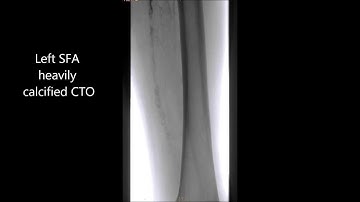

TruePath Popliteal CTO